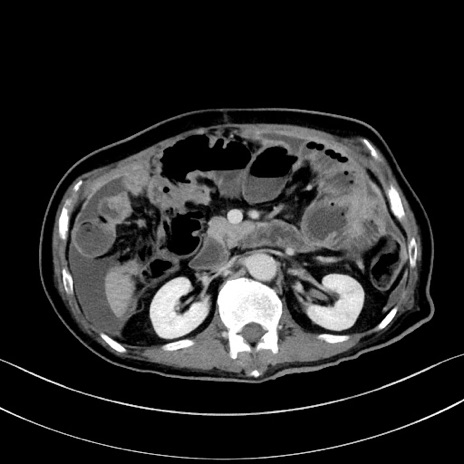

冠状断像

【症例】60歳代男性

【主訴】嘔吐

【現病歴】胃癌にて胃全摘後。食思不振が悪化し、夜中に嘔吐することがある。

【既往歴】胃癌、胃全摘、脾摘、胆摘後

【データ】WBC 5900、CRP 10.56